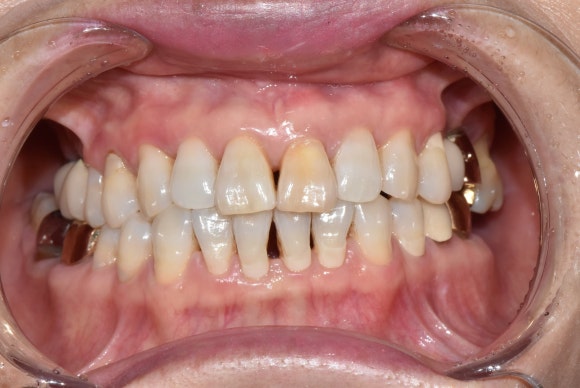

두번째 케이스

왼쪽에 보이는 작은 앞니에 주목해주세요.

이 경우도 마찬가지로 오랜기간 괴사를 겪으면서 짙은 오렌지색으로 변색된 케이스입니다.

마찬가지로 신경치료 후에 미백치료를 시작하였고, 3회차에 치료를 종료하셨습니다.

치료 전 후